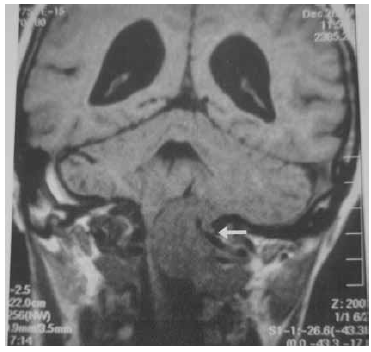

Observe a imagem em corte coronal feita por Ressonância Magnética de crânio, na fase sem contraste.

(Jotz et.al. Tratado de Deglutição e Disfagia no adulto e na criança. p. 257)

Assinale a alternativa que apresenta a avaliação correta da região apontada pela seta branca.